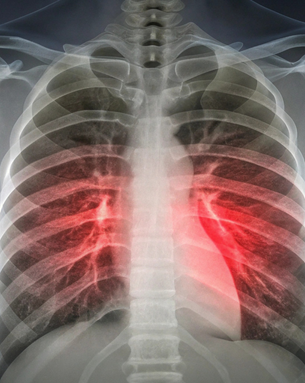

Dr. Bhumika Madhav is a highly skilled Pulmonologist at Apollo Hospitals, Navi Mumbai, with extensive experience in respiratory, sleep, and critical care medicine. Over the years, she has built a strong clinical profile through rigorous training, hands-on ICU experience, and specialized certifications in sleep medicine, pediatric sleep medicine, and allergy–immunotherapy. Her work spans the entire spectrum of lung diseases—from asthma, COPD, interstitial lung disease, and tuberculosis to complex ICU cases, bronchoscopic procedures, and management of sleep-related breathing disorders.

Her service philosophy revolves around accurate diagnosis, evidence-based treatment, and holistic patient care. She believes every patient’s condition is unique and demands a personalized treatment plan that goes beyond just medicines. By combining advanced diagnostic tools such as bronchoscopy, PFT, DLCO, polysomnography, and USG-guided procedures with compassionate counselling, she ensures patients understand their illness and feel confident in their recovery journey.

Holistic diagnosis and treatment for a wide range of lung and breathing disorders.

Advanced Pulmonary Diagnostics & Therapeutic Procedures